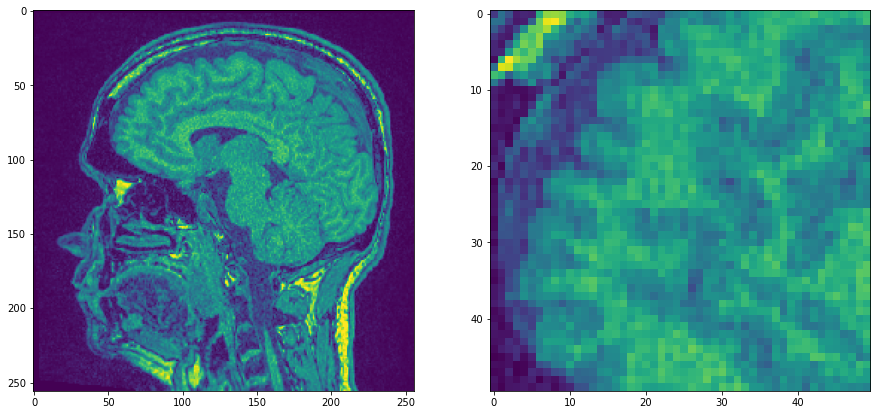

我们从MRT示例数据集的单个平面开始,这个平面噪声相当大,我们将放大查看。

noisy_mri_zoom = noisy_mri[50:100, 50:100]

axs[0].imshow(noisy_mri)

axs[1].imshow(noisy_mri_zoom)